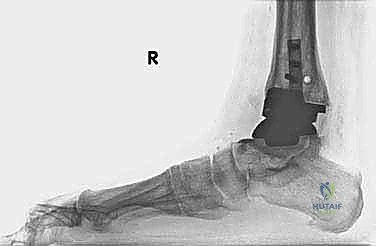

- الأشعة السينية مع تحميل الوزن (Weight-bearing X-rays): لتقييم الزوايا الميكانيكية وتحديد مدى هبوط المفصل أو وجود كسور في الكعب.

* مراجعة المفصل (Revision Arthroplasty): إزالة المفصل القديم وتركيب مفصل جديد مخصص للمراجعة (بسيقان معدنية أطول لضمان الثبات في العظم السليم).

* دمج الكاحل (Ankle Arthrodesis): إذا كان التآكل العظمي هائلاً ولا يسمح بتركيب مفصل جديد، يتم إزالة المفصل الصناعي ودمج عظمة الساق مع عظمة الكاحل باستخدام مسامير وصفائح معدنية وطعوم عظمية.

الخطوة الخامسة: تركيب المفصل الجديد أو الدمج

يتم إدخال المفصل الجديد المخصص للمراجعة، والذي يحتوي غالباً على سيقان (Stems) تدخل عميقاً في عظمة الساق وعظمة الكاحل لضمان الثبات الميكانيكي. في حال وجود كسور في الكعب، يتم تثبيتها في هذه المرحلة.